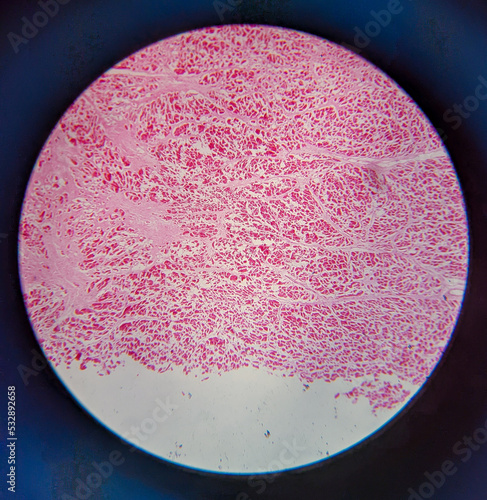

Mikrofotografi - Plakater, Poster, Billeder på lærred